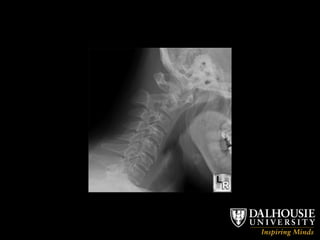

Airway Exam Thyromental Distance (6cm / 3 FB) Jaw Subluxation Mouth Opening (3 FB) Atlanto-Occipital Extension (30 degrees)

Airway Exam ThyromentalDistance (6cm / 3 FB) Jaw Subluxation Mouth Opening (3 FB) Atlanto-Occipital Extension (30 degrees)